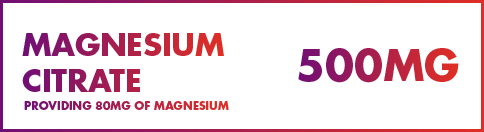

Magnesium plays a vital role in over 300 enzymatic reactions within the body which are required for hundreds of different processes. Due to its far reaching influences, maintaining magnesium levels with BioPharm-X has an extensive range of benefits.

Magnesium is a naturally occurring macromineral and an essential ion for the activation of more than 300 enzymatic reactions. These enzymatic reactions regulate a large number of diverse biochemical reactions within the body, including enzymes that transfer phosphate groups with relation to energy metabolism, muscle function, the transmission of nerve impulses as well as the growth and maintenance of bones.